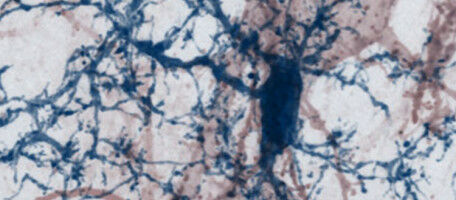

Sciences de la vie - Santé - 25.01.2021

Une équipe de l'UNIGE, de l'Université de Munich et de l'Institut technique de Munich a découvert que la destruction des synapses de la matière grise cérébrale réduisait l'activité des neurones dans le cortex cérébral et constituait un facteur majeur de la progression de la sclérose en plaque. La sclérose en plaques est une maladie inflammatoire chronique du système nerveux central, dans laquelle les cellules nerveuses sont endommagées et détruites par le système immunitaire des malades.